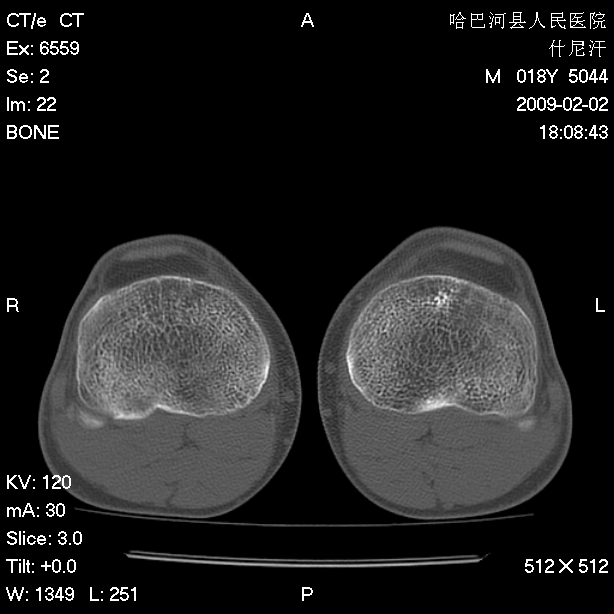

标题: CT17889:外伤后右膝关节反复疼痛3年余 [打印本页]

标题: CT17889:外伤后右膝关节反复疼痛3年余

ct未见明显异常。关节腔未见明显积液,半月板未见明显撕裂。但最好还是mri看看韧带及半月板情况。